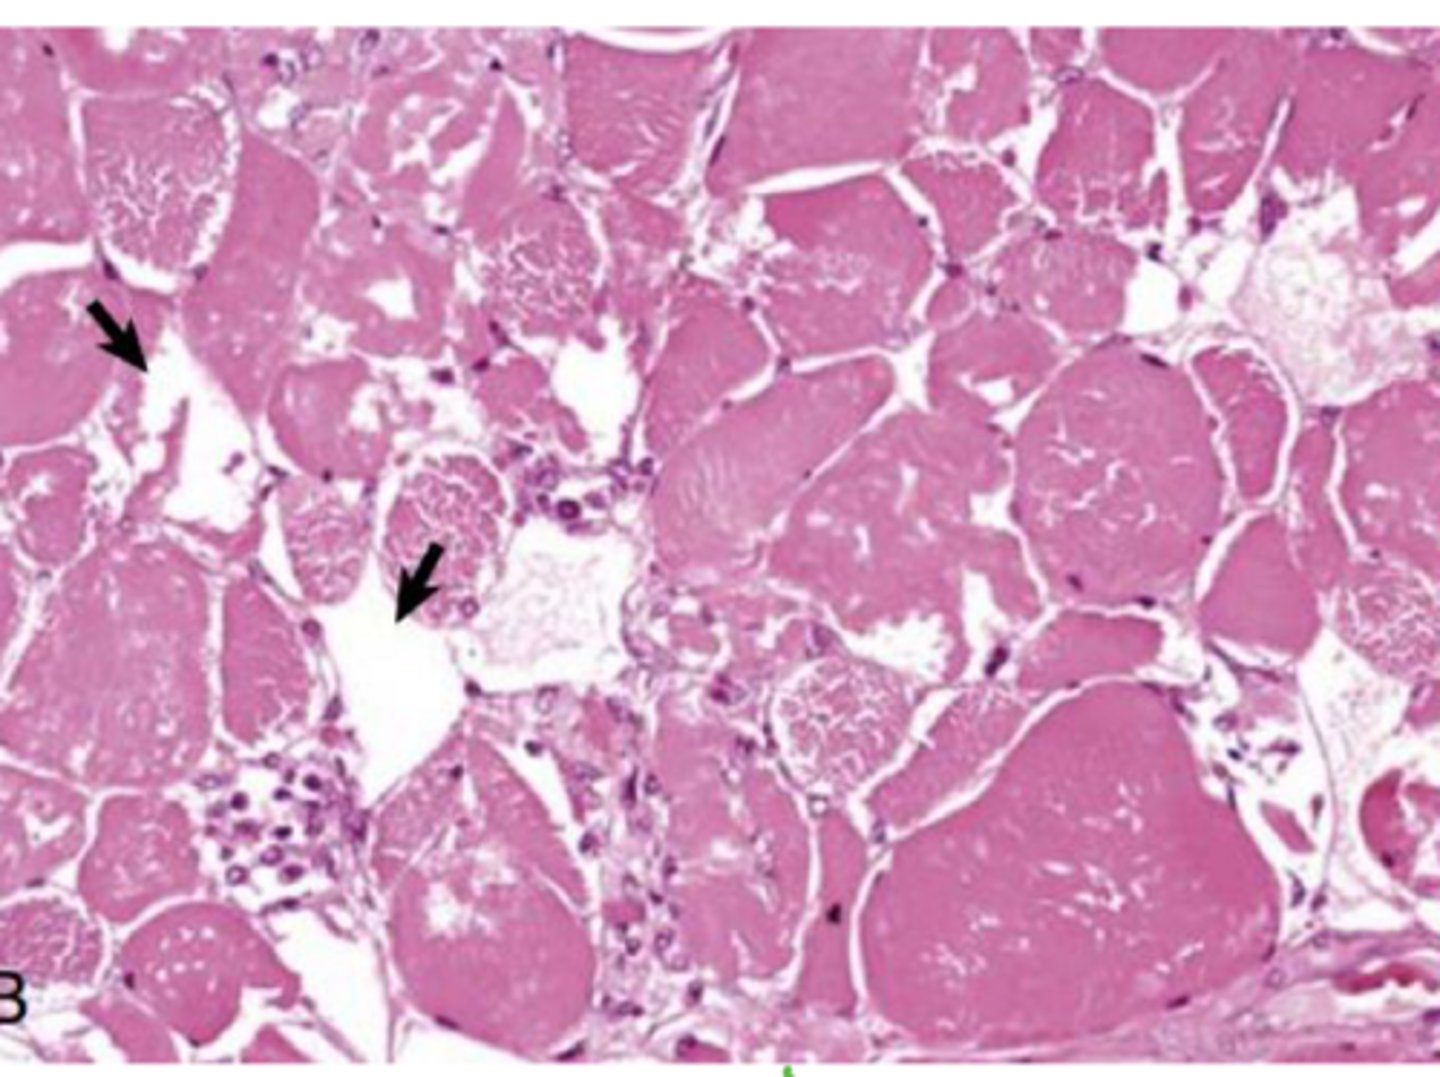

Identify the pathology?

Clostridial myostits - muscle necrosis